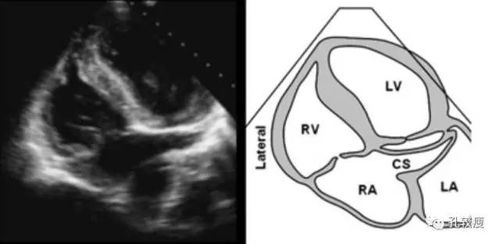

心尖四腔心切面二维超声心动图

心尖五腔心切面:主要用于显示右心室侧壁及调节束▲胸骨旁四腔心

五腔心切面

心尖四腔心

四腔心切面